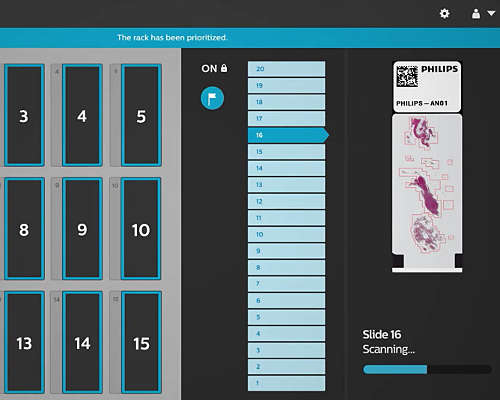

Pathology Scanner SG300

SG300 is designed to accommodate laboratories for high volume labs that want to maximize scanner utilization and further reduce the total cost of ownership per slide by means of overnight scanning. With a high throughput, high first time right rate and load and walk away scanning, the SG300 enables you to digitize your histology samples and obtain high quality clinical diagnostic images for routine use and integrated pathology networks.